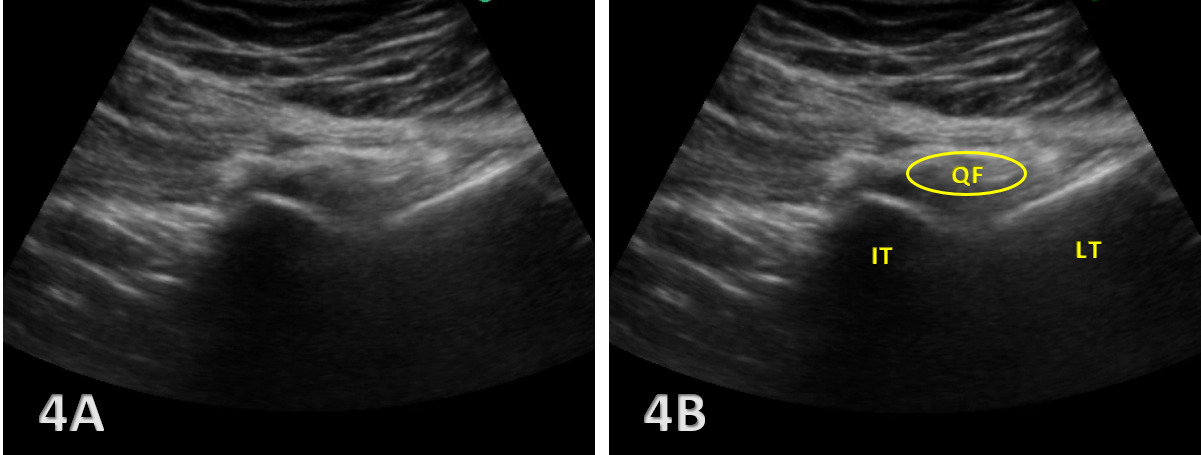

The ischiofemoral space (IFS) is the anatomical interval between the lateral cortex of the ischial tuberosity and the medial cortex of the lesser trochanter of the femur. Within this space lies the quadratus femoris muscle, along with the sciatic nerve and associated vascular structures, all of which are crucial to hip function. Narrowing of the IFS, typically defined as a distance below 1.5 cm, can lead to IFI, a condition characterized by pain and restricted motion in the posterior hip. In addition to the IFS, the quadratus femoris space (QFS)the distance between the hamstring origin on the ischial tuberosity and the insertion of the quadratus femoris muscle—is another critical measurement in assessing IFI.

When the IFS becomes narrowed, compression of the quadratus femoris muscle and the sciatic nerve can occur, leading to the hallmark symptoms of IFI, including deep posterior hip pain and potential nerve-related symptoms. Normal IFS values range from 2 to 2.5 cm, and accurate measurement of this space is crucial for diagnosis. Given that the actual space is highly variable based on the gait cycle or what position the hip is in during testing, and MRI tends to overestimate the measurement,6 MSKUS is the perfect tool for assessing this space either statically or dynamically. Dynamic hip MSKUS can corroborate IFI and space with the change in position of the lower extremity, as well as to assess whether the symptoms are due to other potential causes.7 MSKUS is an invaluable tool for visualizing these structures, offering dynamic, real-time imaging that enhances diagnostic accuracy in cases of suspected IFI .

Narrowing of the IFS: A key indicator of IFI is the decreased distance between the ischial tuberosity and the lesser trochanter. Ultrasound allows for precise measurement of the IFS, particularly at the point of greatest narrowing, which is critical for diagnosing impingement. IFS measurements by MSKUS have been shown to be very similar to those obtained with MRI.15

Quadratus Femoris Edema or Atrophy: MSKUS can identify increased echogenicity in the quadratus femoris muscle, which suggests edema or early degeneration. This muscle is most involved in IFI and serves as a crucial diagnostic marker.

Dynamic Testing: One of the strengths of MSKUS is its ability to assess the IFS during hip movement, such as extension and external rotation. This real-time imaging allows clinicians to directly observe impingement of the quadratus femoris during dynamic motion, further aiding in diagnosis.